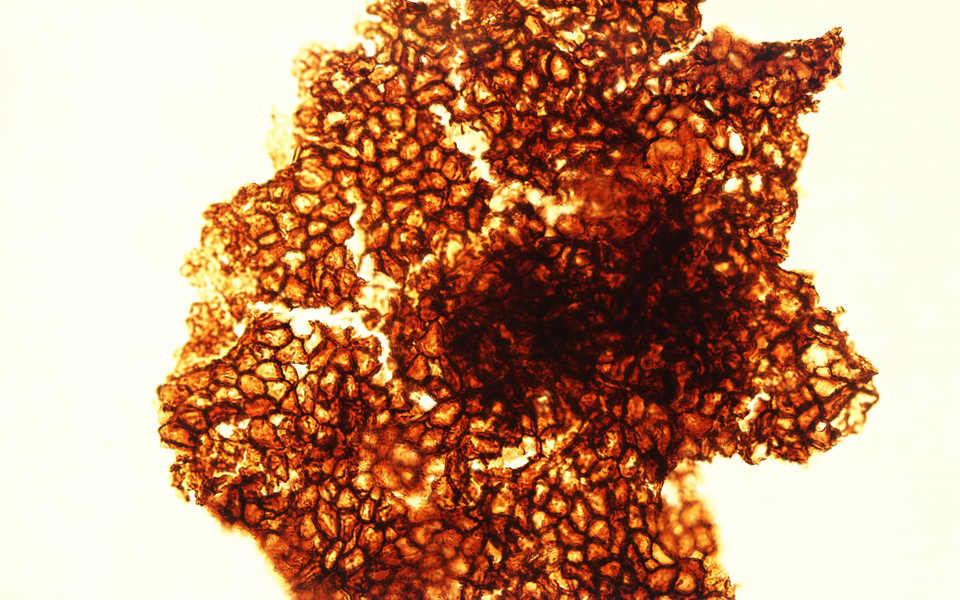

Αρρώστια από αρρώστια διαφέρει. Το Αλτσχάιμερ πάντως, από το οποίο πάσχουν δεκάδες εκατομμύρια άνθρωποι στον κόσμο, είναι ίσως εκείνη που διαφέρει περισσότερο από όλες τις άλλες.